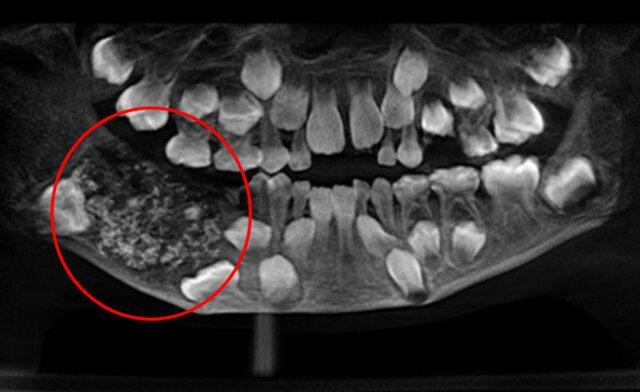

پزشکان پس از اسکن و عکسبرداری از فک این پسربچه با کیسه ای در فک پایینی او روبرو شدند که به طور غیرطبیعی پر از دندان بوده است.

به گفته پزشکان در مجموع 526 دندان از 0.1 میلی متر تا 15 میلی متر در این کیسه وجود داشت که حتی کوچک ترین آن ها نیز دارای تاج دندان، ریشه و مینای دندان بوده است.